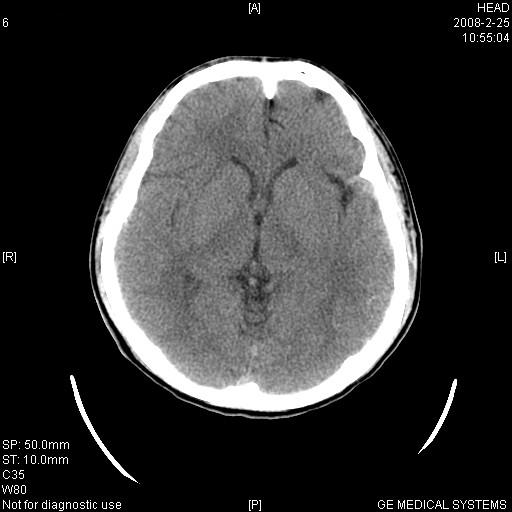

男,23岁,下颌部外伤一天,主因头痛、头晕、左面部麻木来院。两年前有外伤史,至左眼视力差。余无异常。骨窗未见异常故未上传。

左侧海绵窦区高密度肿块影,颈动脉—海绵窦瘘不排除,不过患者眼上静脉无增粗,无突眼,也不能排除血管瘤的可能,建议增强扫描。外伤病人应该有骨窗。

1、左侧海绵窦血管瘤。2、左顶后叶高密度影,建议增强扫描,血管瘤可能,脑白质异位待排。

1、左侧鞍旁海绵窦区稍高密度占位---左侧海绵窦血管瘤或脑膜瘤,以前者可能性大。2、左顶后叶高密度影,血管瘤可能,脑白质异位待排。3建议mri检查

左侧鞍旁海绵窦区稍高密度肿块,境界清楚;结合病史,不排除左侧颈内动脉海绵窦瘘可能。须与动脉瘤,海绵状血管瘤及左侧鞍旁脑膜瘤相鉴别。建议:行ct增强扫描检查,必要时行dsa检查。

左侧海绵窦区高密度肿块影,考虑颈动脉—海绵窦瘘,病人临床左眼视力差,头疼、头晕也较符合。但确诊最好还是强化,有战友说病人的眼上静脉不粗,主要是楼主没有扫到。建议增强的时候薄扫一下!!